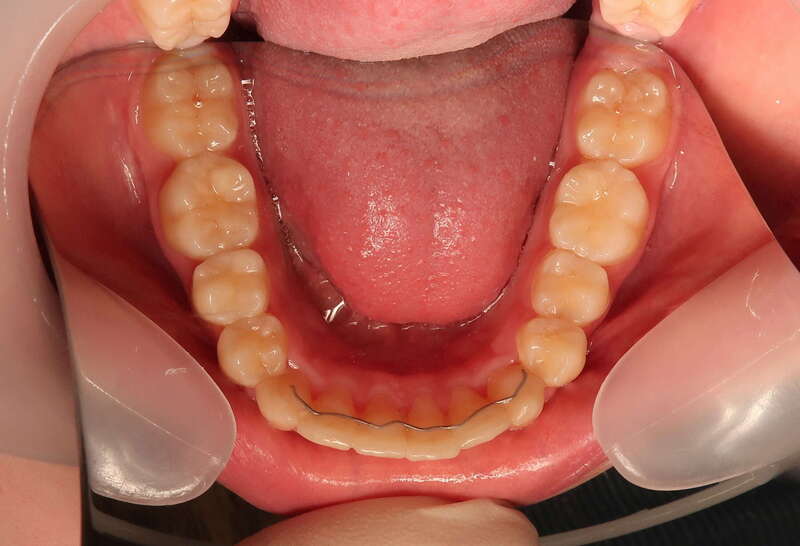

Cas n°9 traité par multi-attaches - adolescent

Ce cas d'adolescent illustre une stratégie de développement d'arcade réussie. Le patient présentait un encombrement massif et des inversions d'articulé rendant l'occlusion instable.

Le traitement a été réalisé avec des multibagues autoligaturantes, choisies pour leur capacité à générer des forces légères et continues, idéales pour l'expansion transversale. Cette approche a permis de corriger l'encombrement et les inversions d'articulé sans extractions dentaires, en remodelant simplement la forme des arcades.

Résultats clés :

• Transformation d'arcade : Passage d'une arcade étroite et encombrée à une arcade large et fonctionnelle.

• Occlusion optimale : Rétablissement d'un engrènement sain, protégeant les dents contre les usures anormales.

• Esthétique naturelle : Le sourire est élargi, harmonieux et parfaitement intégré au profil du patient.

C'est une démonstration de l'efficacité biologique de l'orthodontie moderne, qui privilégie la conservation dentaire et le respect des structures osseuses.